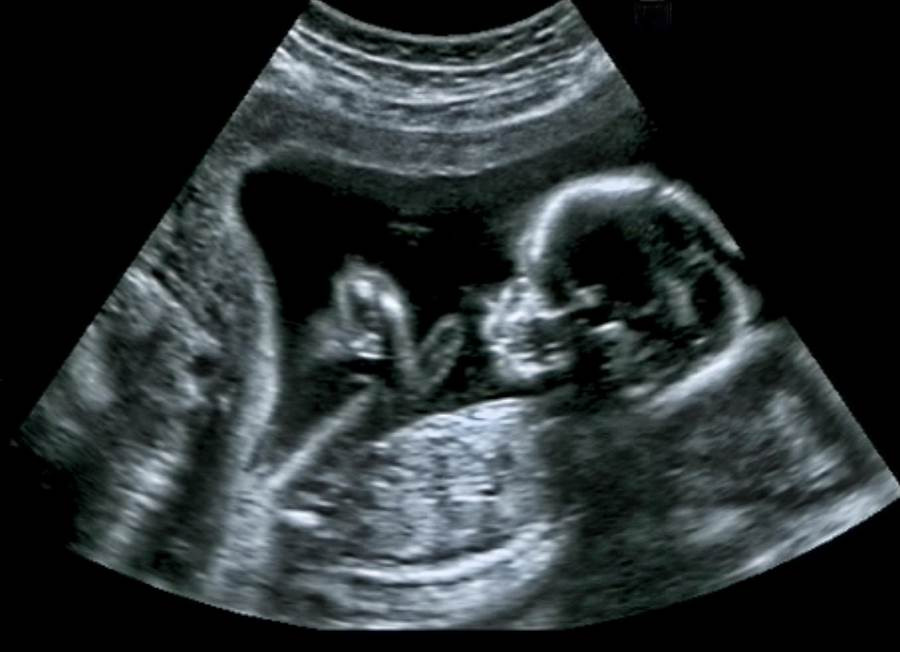

Theo trang Flowserve News, cô Farrah Roth, 42 tuổi, ở Oklahoma, Mỹ khi siêu âm thai ở tuần 27 đã phát hiện con trai mình liên tục thè lưỡi.

Thế nhưng những lần siêu âm thai sau đó, thai nhi vẫn liên tục lè lưỡi, các bác sĩ phát hiện có gì đó không ổn và ca sinh mổ đã được thực hiện. Cậu bé Baker Roth và chiếc lưỡi khổng lồ ra đời trong sự ngỡ ngàng của mọi người.